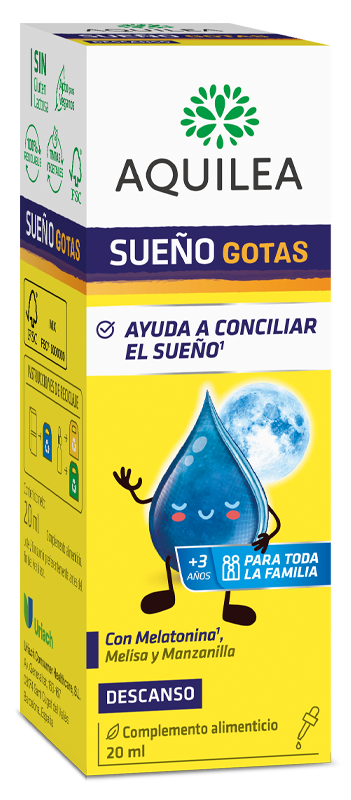

Todos necesitamos dormir unas determinadas horas al día. El ciclo de sueño-vigilia que se repite como una constante en nuestras vidas, está marcado por un "reloj biológico" interno que nos dicta cuándo despertar y cuándo dormir. A este ciclo se le denomina ritmo circadiano y abarca 24 horas, divididas en 8 para el sueño y 16 para la vigilia. Una buena opción para no tomar comprimidos es la melatonina en gotas sobre todo para los más pequeños con problemas para conciliar el sueño

Aquilea Sueño gotas, es un complemento a base de melatonina y además contiene Manzanilla y Melisa. La melatonina contribuye a disminuir el tiempo necesario para conciliar el sueño, con una ingesta de 1 mg de melatonina poco antes de dormir.